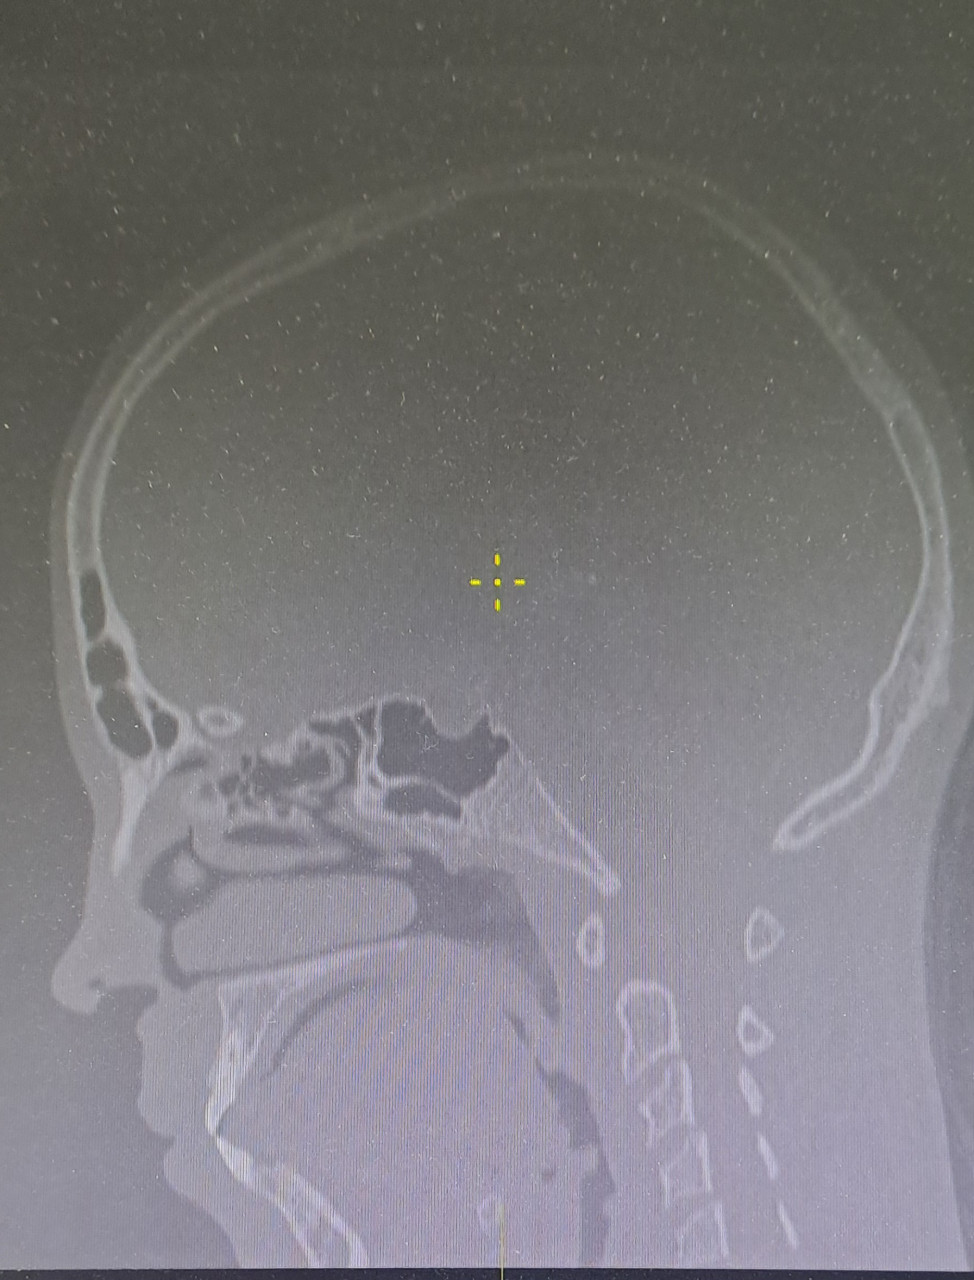

Ребенку тольтко 13 лет исполнилось сделали кт головы, как врач сказал, но оказалось там все обоучили и голову и лиц скелет и шею L=25см. DLP 752 CTDI 30мГр. Пересчет в эф.дозу сделали коэфициентом для головы, а не общим голова/шея, чтоб снизить дозу. Как потом оказалось на всякий случай. Шею облучали дозой для головы 30 мГр, хотя для шеи она в 3 раза ниже должна быть. Какое для нас это горе не передать словами. Прошу подсказать 1)сколько шейных позвонков вошло в зону облучения2) попала ли щитовидка и какое облучерие она получила даже рассеивающее, защиту не надевали 3) гортань, слюные железы также облучили дозой выше нормы для костей 4) подскажите про расчет SSDR реально поглощенная доза по диаметру головы, если фантом 16 см, а головы больше диаметром эффектианым, то реалтно рогл.доза меньше CTDI, а для шеи? Ведь у нее диаметр меньше, значит она еще больше 30 мГр поглотила? 5) какая дрза облучени косного мозга получилась от облучерия головы и шеи? 6) по кт снимкам поле fov 25 см, а анатомическая область 23 см от низа до макушки. Над голоаой 2 см пустоты, куда делось облучение по спирали,прошедшее в пустоте над головой? 7) про дополнительные ротации в начале и в конце облучения. Это значит CTFIx2=60мГр в начале и в конце??? 7)какими анализами сейчас контролировать последствия, научные статьи подтверждают факт ужасного влияния кт. Голова от кучи вопросов разрывается. В больнице говорят- так получилось.